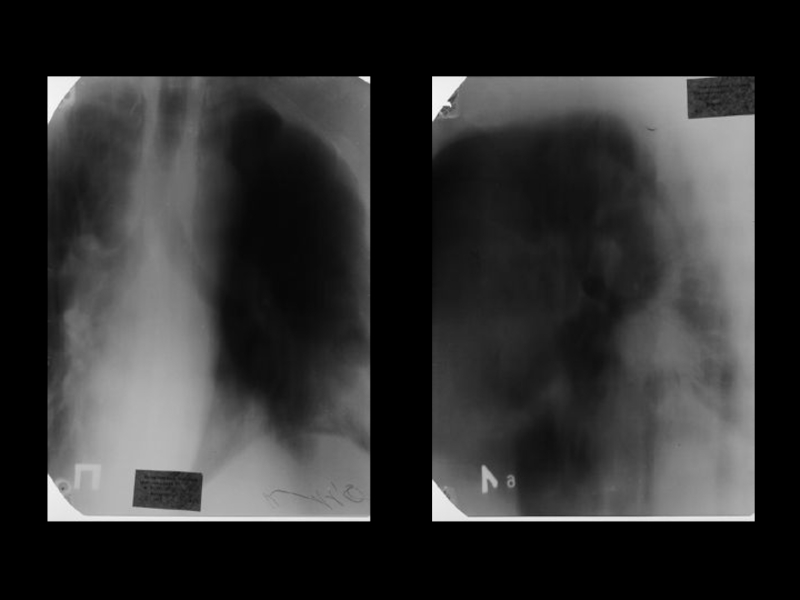

Центральный рак легкого

ЛУЧЕВАЯ ДИАГНОСТИКА РАКА ЛЕГКОГО

АКТУАЛЬНЫЕ ВОПРОСЫ РЕНТГЕНОЛОГИИЦентральный рак легкогоЛУЧЕВАЯ ДИАГНОСТИКА РАКА ЛЕГКОГО